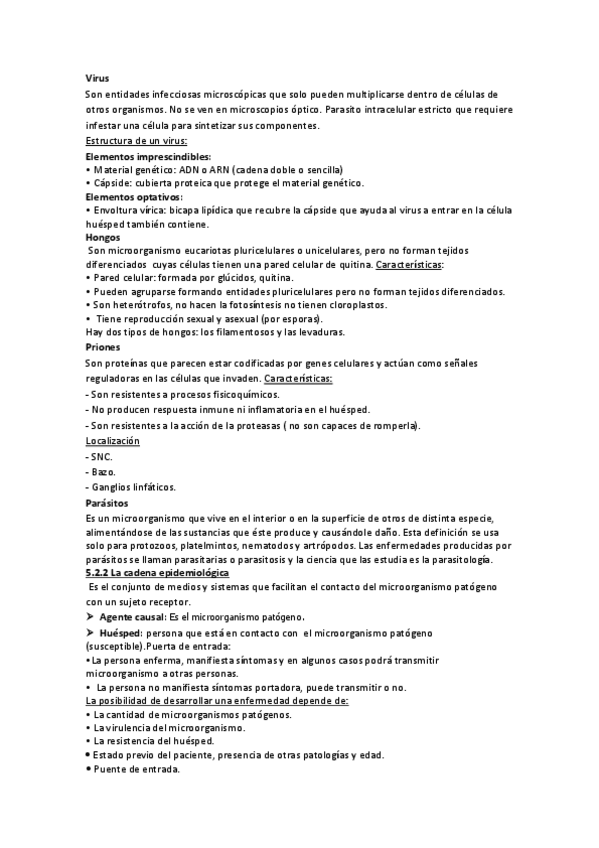

He publicado nuevos apuntes de Fisiopatología general: Tema-5-infecciones-y-neoplasias.pdf

He publicado nuevos apuntes de Fisiopatología general: Tema-4-La-enfermedad.pdf